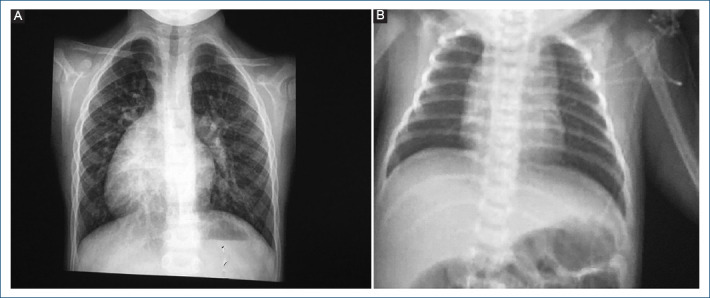

目的:心房-心室和心室-动脉双不协调(DD)或大动脉转位矫正术是一种罕见的心脏疾病,每1000个活产新生儿中就有0.02-0.07个患有此病。本研究旨在描述一系列 DD 患者的诊断、治疗和演变情况:方法:对过去 22 年中诊断出的 DD 患者的病历进行回顾性和描述性研究。研究采用了描述性统计方法。数字变量采用均值和标准差,分类变量采用频率和百分比:22 年中研究了 30 名患者,男性与女性的比例为 1.5:1,平均年龄为 20 个月。24/29(82.7%)名患者的病位为室间隔缺损。室间隔缺损是最常见的病变,占 25/29 例(86.2%),三尖瓣关闭不全占 70%。四名患者被诊断为肺动脉高压。20%的患者患有房室传导阻滞。一名患者患有沃尔夫-帕金森-怀特综合征。70%的患者接受了手术治疗。其中8人接受了格伦手术(26.6%),4人接受了丰坦手术(13.3%)。随访时间从1个月到17年不等。5人死亡(16.6%)。在随访的25名患者中,18名患者(72%)心室功能正常,5名患者为二级Ross分级(20%),2名患者为三级(8%):结论:这些患者的生活质量正在改善,但文献中对实施最合适手术的理想时间仍存在争议。

Results: Thirty patients were studied in 22 years with a ratio of 1.5:1 for men, with a mean age of 20 months. The situs was solitus in 24/29 patients (82.7%). Ventricular septal defect was the most frequent lesion in 25/29 (86.2%) Tricuspid insufficiency in 70%. Four patients diagnosed with pulmonary atrial hypertension. With atrio-ventricular block 20%. One with Wolff-Parkinson-White syndrome. Surgical treatment was carried out in 70% of patients. Eight with Glenn procedure (26.6%) and 4 with Fontan surgery (13.3%). Follow-up ranged from 1 month to 17 years. Five died (16.6%). Of the 25 patients in follow-up, 18 patients (72%) had normal ventricular function, 5 with Grade II Ross classification (20%) and 2 in Grade III (8%).